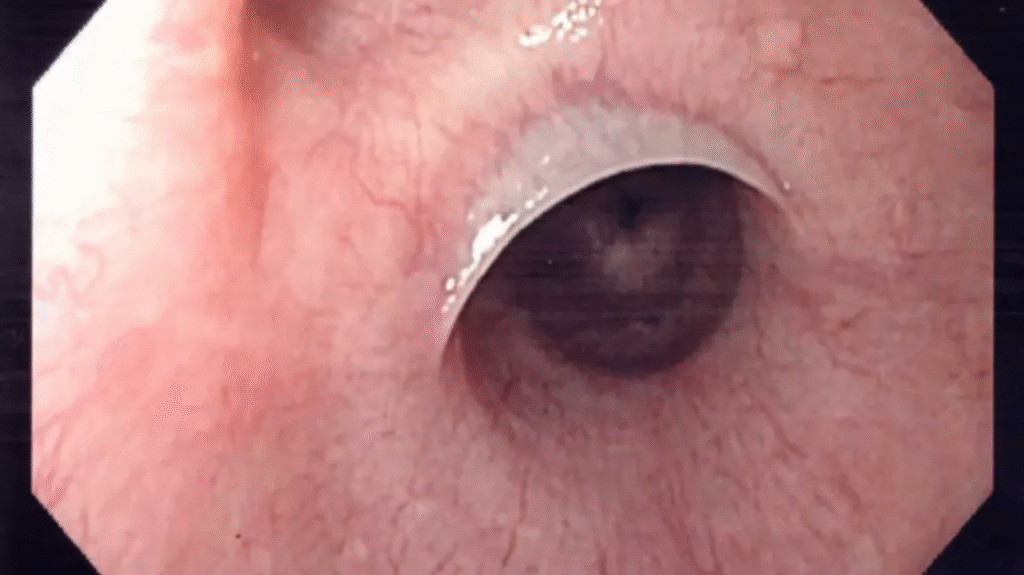

- Dünne Schleimhaut Membranen im Ösophagus → mechanische Engstellen.

- Schatzki-Ring (distal, meist mit Hiatushernie) → Dysphagie für feste Speisen.

- Diagnostik: Breischluck oder Endoskopie.

- Therapie: Endoskopische Dilatation, Eisen-Substitution (bei PVS).